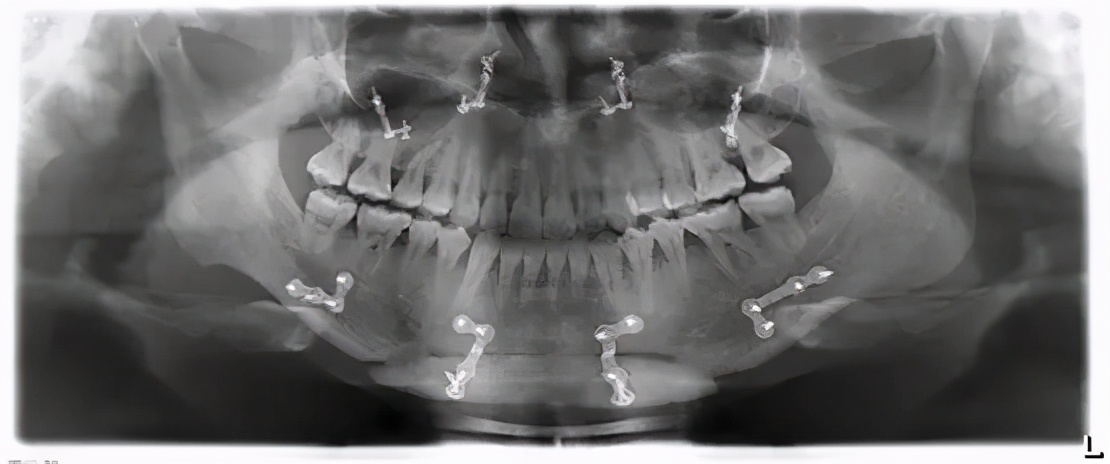

偏颌畸形的治疗,通常需要经过正畸-正颌手术联合治疗来获得功能和外貌俱佳的效果。因为正颌外科手术要通过移动颌骨来达到手术目的,在移动颌骨的同时,牙齿也会相应发生移动,因此需要外科医生与正畸医生一起配合,才能达到“外形与功能兼具”的治疗目的。

一般是【术前正畸——正颌手术——术后正畸】的顺序。即通过正畸治疗排齐牙列,为正颌手术做好准备。再经过正颌外科手术,将异常的颌骨关系矫正,取得满意的矫治效果,正颌手术之后还要进行正畸以稳定术后效果。

另外,术前正畸耗时较长,对于符合条件的求美者,如牙齿排列、咬合关系较好的前提下,可以采取手术先行策略,先进行正颌手术再做正畸治疗。

需要注意的是,正颌手术只有具备资质的医院可以进行。正规医院在术前会经过数字化手术辅助设计,可以有效提高正颌手术的精准度和效率,从而降低手术风险,保证手术效果。因此建议求美者选择正规医院,谨慎就医。